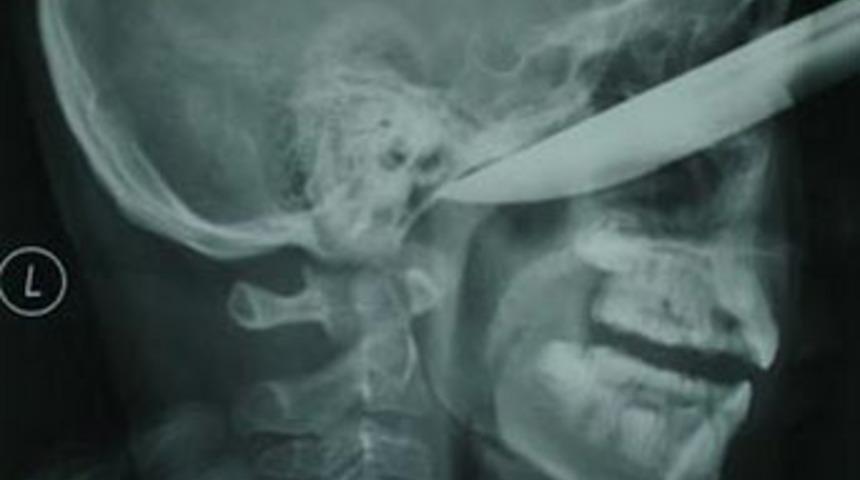

Çin'de kaza sonucu yüzüne 20 santimetrelik bıçak saplanan erkek çocuk şans eseri hayatta kaldı.

13 yaşındaki Ren Hanzhi'nin sol yanağından çok derine saplanan bıçak inanılmaz bir şekilde gözüne ve beynine bir zarar vermedi. Doktorlar bıçağı başarılı bir şekilde çıkartırken, çocuğun tamamen iyileşmesi bekleniyor.

Elma soyarken 20 santimetrelik bıçağın üzerine düşmesi sonucu hastanelik olan çocuğun yüzünde 7 santimetre derinliğinde bir yara açıldı. Çocuğun yaklaşık bir ay içinde iyileşmesi beklenirken, Ren'in babası, "Elmayı soyarken kanepeye doğru yürüyordu. Aniden kayıp düştü ve bıçak yüzüne saplandı" diye konuştu.